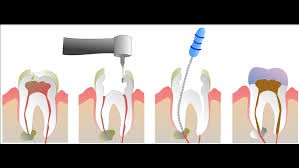

Il trattamento endodontico prevede la rimozione fino alle radici del dente della polpa danneggiata e nella sua sostituzione con un’otturazione permanente. In questo modo vengono elimitai tutti i batteri che si erano accumolati e che hanno causato il danno e il dente una volta riparato potrà tornare a svolgere la sua funzione.

Il trattamento prevede l’utilizzo dell’anestesia locale per neutralizzare il dolore e tenerlo sotto controllo, a seguito della terapia nelle ore successive è possibile sentire un indolezimento più o meno persistente che può essere controllato grazie all’assunzione di analgesici.